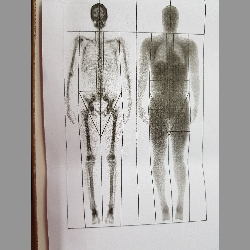

What is DEXA scan?

Updates the reader on DEXA scan and its utilities.

What is DEXA scan?

Updates the reader on DEXA scan and its utilities.